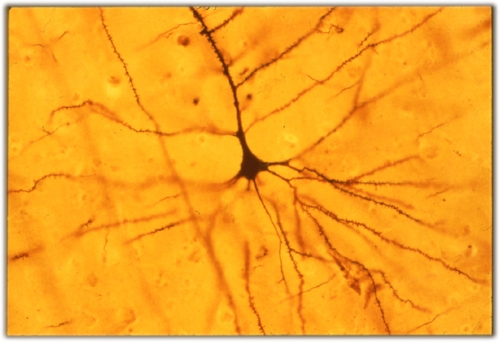

The Imitation Brain: Three Ways to Make the Most of Mirror Neurons

Imitation is the sincerest form of flattery. Is it possible that imitation is also the pathway to learning? In the late 1990s and early 2000s, scientists at the…